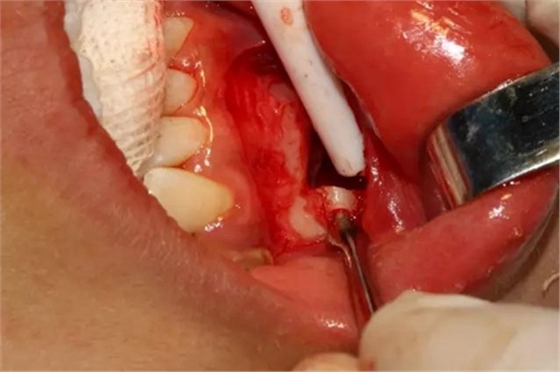

橫斷牙冠,注意深度的把控

為了減少骨創(chuàng),“T”型分割牙冠

去除冠部